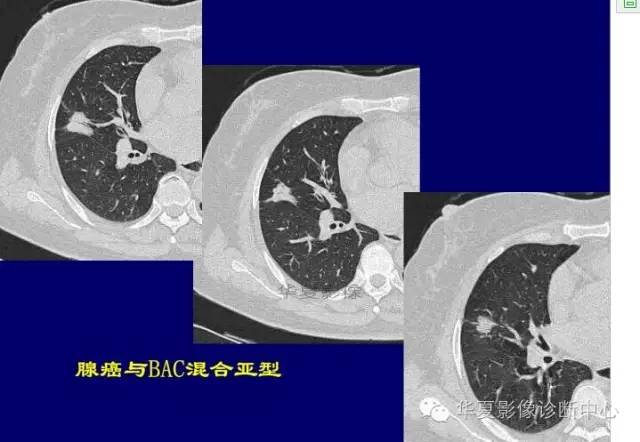

周围GGO边界清楚,分叶征、胸膜凹陷征、含气支气管,混合型GGO

磨玻璃结节良恶性影像分析策略 混合型,边界清楚、分叶征,考虑肺癌

磨玻璃结节良恶性影像分析策略 磨玻璃结节良恶性影像分析策略磨玻璃结节良恶性影像分析策略 其中血管显示清楚,GGO

边界清楚,分叶征,空泡征